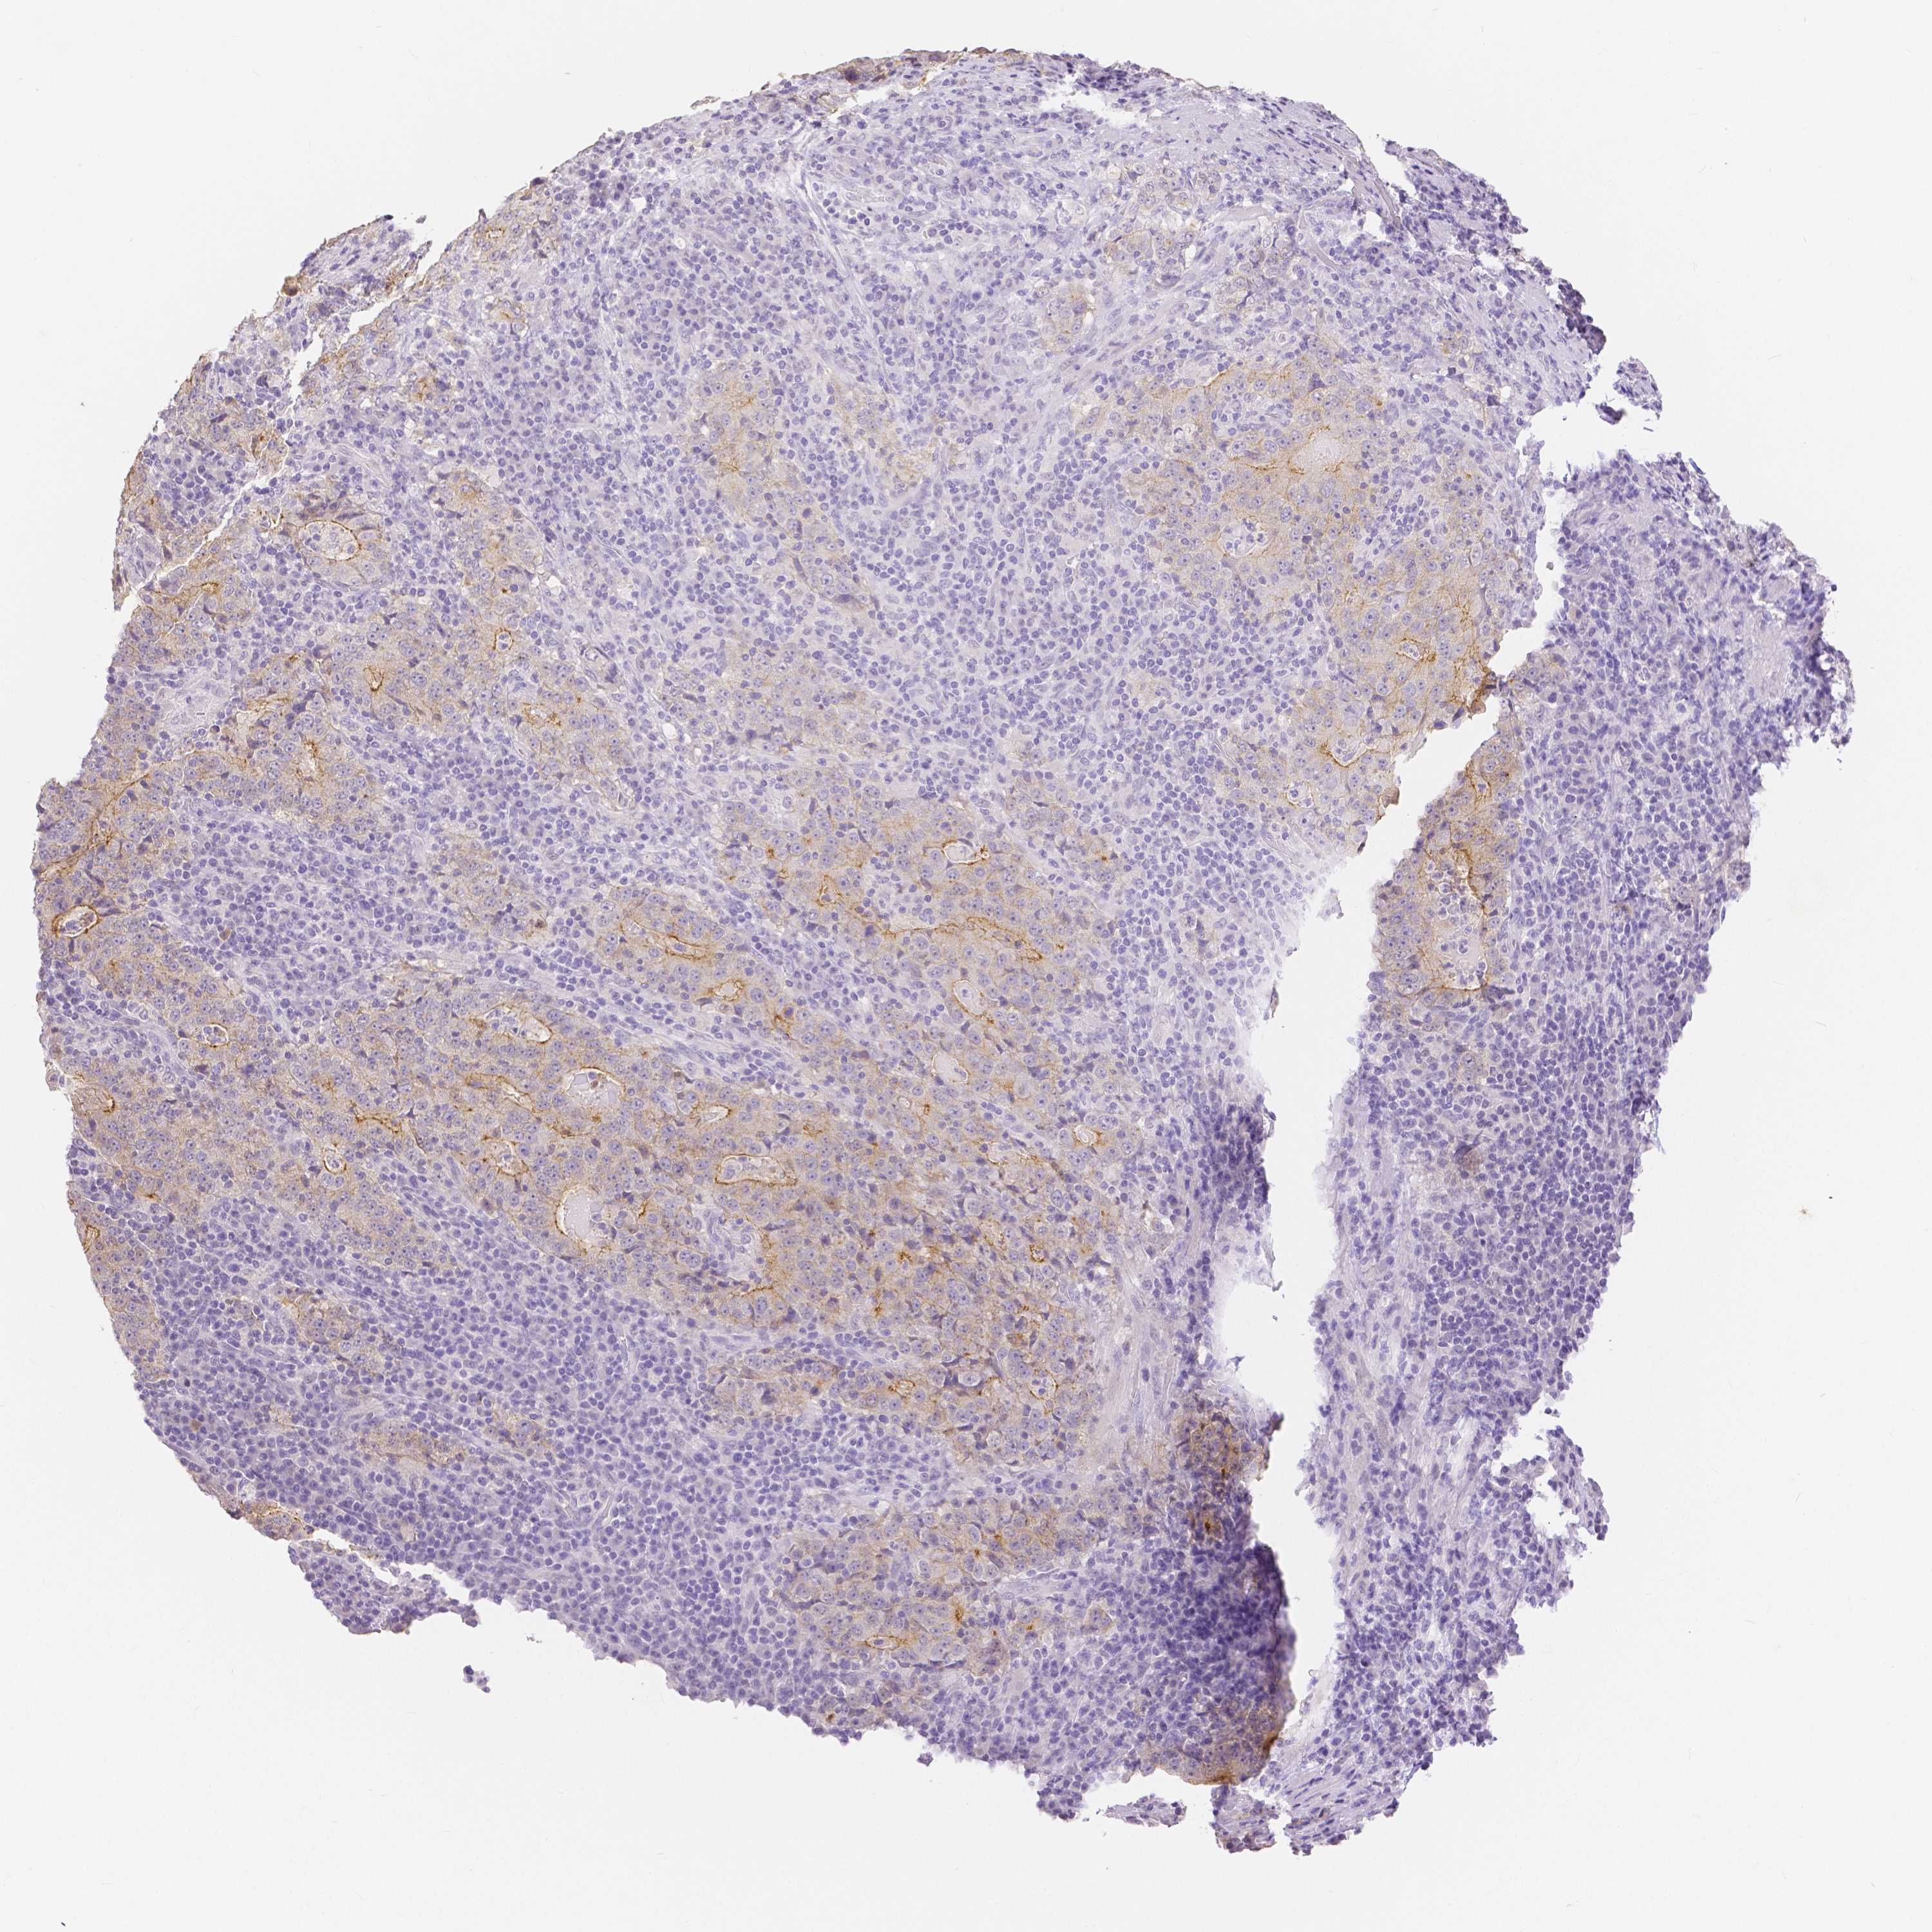

STOMACH CANCER - Protein expressioni

A mouse-over function shows sample information and annotation data. Click on an image to view it in a full screen mode. Samples can be filtered based on level of antibody staining by selecting one or several of the following categories: high, medium, low and not detected. The assay and annotation is described here.

Note that samples used for immunohistochemistry by the Human Protein Atlas do not correspond to samples in the TCGA dataset.

Antibody stainingi

Antibody staining in the annotated cell types in the current human tissue is reported as not detected, low, medium, or high, based on conventional immunohistochemistry profiling in selected tissues. This score is based on the combination of the staining intensity and fraction of stained cells.

Each image is clickable and will lead to virtual microscopy that enables deeper exploration of all samples and also displays staining intensity scores, fraction scores and subcellular localization as well as patient and tissue information for each sample.

HPA005933

CAB013075

CAB068212

CAB068213

CAB068214

Adenocarcinoma, NOS

Adenocarcinoma, High grade